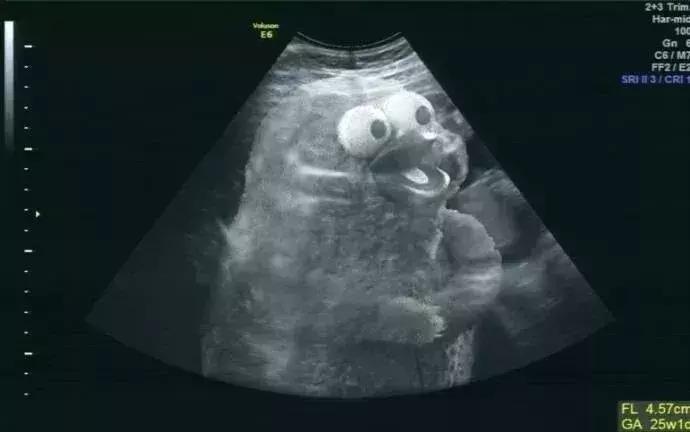

06 心脏、胎儿超声检查

心脏、胎儿超声是超声检查的优势项目,心脏和胎儿异常往往都是通过超声检查出来的,先天性和后天性心脏病以及心脏功能评估,超声检查是最具优势的方法,也是超声检查的常见内容。

胎儿超声检查更是超声检查的独有优势,20年前大家还不太能接受超声胎儿检查,担心对孩子有影响,不过现在大家都有了超声孕检的观念,在孕期中孕大排畸检查(三级筛查)已经广为大家所接受,对国家优生优孕有重大的促进作用。不过早中孕系统筛查也非常重要,而目前仍未被大家所重视。

提示:早中孕期胎儿超声筛查是十分有必要的。

许多严重的胎儿畸形,如单心室、心室发育不良、心内膜垫缺损等,都可以在早中孕周被筛查出来,所以早中孕的检查非常重要。但仍需要有一定的技巧和技术依赖性,目前仍掌握在少数高水平超声医生手上。